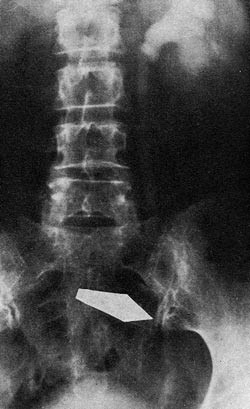

Urin: sp.v. 1012, protein+, Esbach 0,2 , Guajak-. Mikroskopi: Tallrike leukocytter, staver og kokker i korte kjeder og diploform. TB-. Rest-N 50 mg/100 ml. Urografi: Høyre nyreskygge mangler. Venstre nyreskygge noe stor. Noe forsinket utskillelse idet det 7 minutter etter injeksjon av 20 ml Nycotrast bare er antydning til kontrast i enkelte calyces, etter 30 minutter god fylling. Nyrebekkenet noe utvidet med plumpe calyces. Ureter dilatert, ca. 1 cm bred helt ned til blæren, men området foran sacrum kommer ikke fram på grunn av svak kontrastskygge. Dårlig fylling av blæren etter 1/2 time. R: «Manglende høyre nyre. Hydronephrosis sin. Nedsatt nyrefunksjon» (B. Medby) (fig. 1). Cystoskopi viste et rundt og litt trangt venstre ureterositum, ved kromoskopi kom svak blåfarge i repriser etter 35 minutter. Ureterkateteret gikk 11cm opp, selv det tynneste kateter lot seg ikke føre lenger opp.